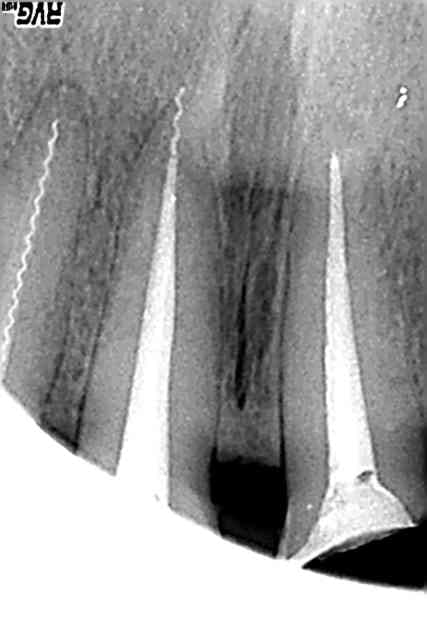

C'est une technique de transfixation apicale ?

ça passe en HN ?